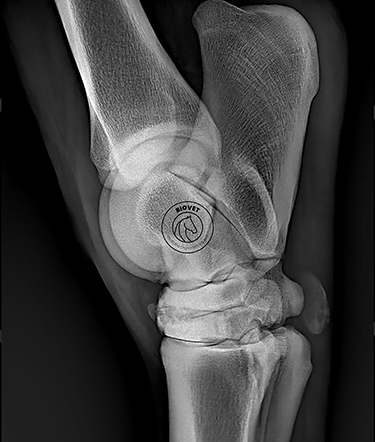

Cualquier articulación puede sufrir artrosis, pero obviamente hay articulaciones en las que es más común.

Por ejemplo, si nos centramos en los miembros anteriores del caballo, pues las articulaciones distales son las más afectadas. Como, por ejemplo, puede ser la articulación interfalangiana distal, que es la articulación de la corona del casco. También es frecuente en la articulación del menudillo.

En los posteriores puede afectarse la articulación del corvejón, que es lo que se conoce en el mundo del caballo como esparaván.